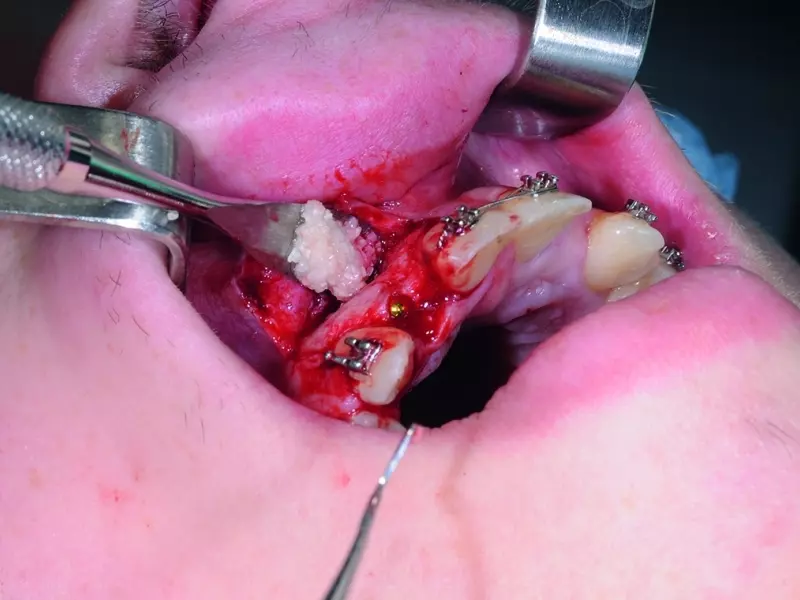

Zabieg przeprowadzono w znieczuleniu miejscowym. Z cięcia na szczycie części zębodołowej żuchwy od strony policzkowej poprowadzonego do mezjalnej powierzchni zęba 37. w jego kieszonce odwarstwiono płat śluzówkowo-okostnowy pełnej grubości (płat kopertowy) (zdj. 26). Następnie wiertłem różyczkowym wykonano otwór osteotomijny, tak aby odsłonić w pełni koronę zęba (zdj. 27). Przy zdejmowaniu tkanki kostnej należy pamiętać o zachowaniu 2 mm marginesu kości oddzielającej otwór od drugiego zęba trzonowego. Dzięki temu status periodontologiczny drugiego zęba trzonowego jest niezaburzony. Przecięto koronę zęba wzdłuż jej długiej osi wraz z rozseparowaniem korzeni (zdj. 28). Następnie usunięto korzeń dystalny wraz z dystalną częścią korony (zdj. 29). Koronę w części mezjalnej odcięto od korzenia, a następnie usunięto najpierw część koronową, a potem korzeń (zdj. 30). Wyłuszczono mieszek zęba. Ranę zaopatrzono szwami (zdj. 31).

Zabieg wykonano w osłonie antybiotykowej (klindamycyna w dawce 600 mg godzinę przed zabiegiem) z następczą antybiotykoterapią (300 mg klindamycyny co 8 godzin).